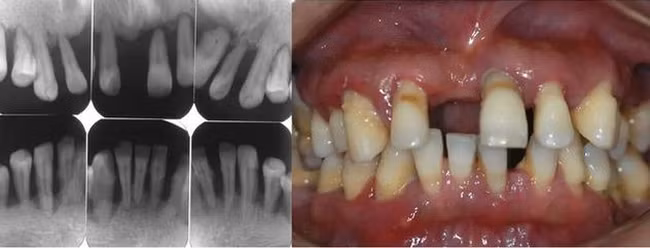

Cách đây 2 năm, Tiểu Trần (tên bệnh nhân đã được thay đổi) đã đến gặp bác sĩ với tình trạng sưng và đau nướu. Khi đó cậu được chẩn đoán là bị bệnh nha chu. Nghĩ rằng mình "ổn", bệnh viêm nha chu không có gì đáng ngại, Tiểu Trần đã từ chối điều trị.

Sáu tháng trở lại đây, thấy răng bị lung lay, kèm theo tình trạng chảy máu khi đánh răng và sưng đau nướu nhiều lần, uống thuốc kháng viêm không thuyên giảm, Tiểu Trần đã đi khám lại.

Bác sĩ điều trị cho anh nói rằng răng anh lung lay như vậy là do xương ổ răng gần như không còn được bọc chắc chắn nữa. Bác sĩ quyết định phải nhổ tất cả răng của anh để tránh tình trạng bệnh nghiêm trọng hơn.

Người đàn ông 31 tuổi đi khám vì răng lung lay, nhưng bác sĩ lại nhổ tất cả răng vì sai lầm từ 2 năm trước của anh - Ảnh 1.